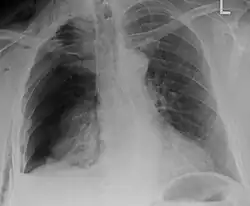

| An X ray showing multiple old fractured ribs of the person's left side as marked by the oval | |

Illustration showing rib fracture at 3rd, 4th and 5th rib -

Right sided pneumothorax and rib fractures -

Two broken ribs as seen on parasagittal CT